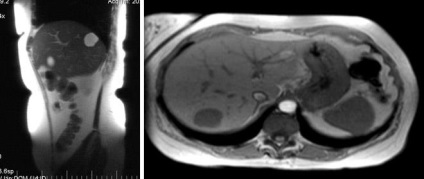

Egy egyszerű ciszta máj

Több máj- hydatid cisztákat és ciszta egység a lépben